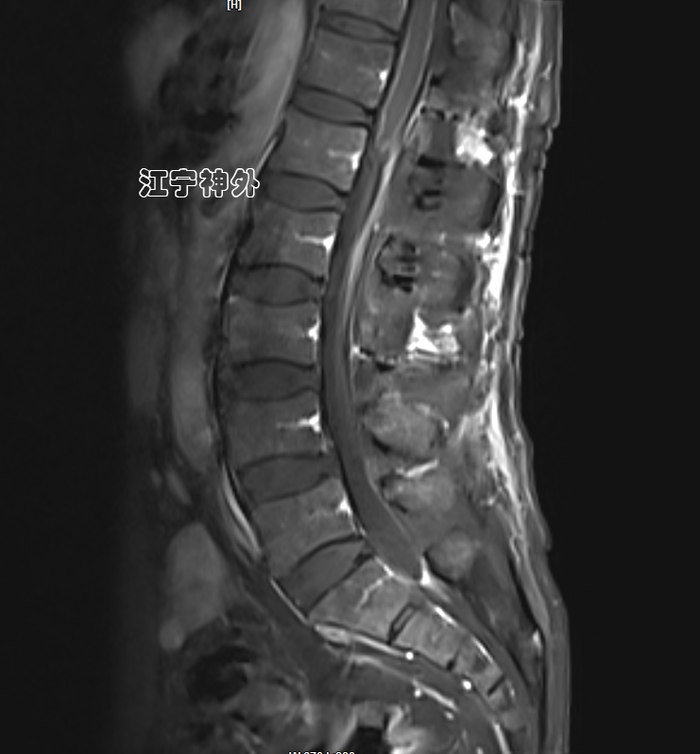

郑主任阅片发现,肿瘤位于胸10水平,属于髓外硬膜下病变,增强不均匀,边界清晰,位于脊髓的左后,脊髓被推向右前方。

经过术前准备,于2月3日在全麻下行肿瘤切除术,手术非常顺利,肿瘤完整全切,根据神经电生理监测,脊髓和神经根保护良好。

术后磁共振显示肿瘤全切,无任何残留;术后两周拆线出院,行走、大小便功能正常,无神经功能缺损。术后病理提示神经鞘瘤。